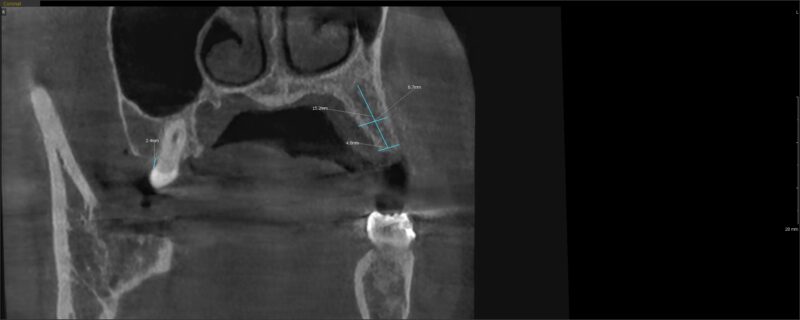

I have another case here with a buccal defect on tooth # 13. Pt has been wearing a flipper for over 10 years.

Looking at the insufficient B-L width at 4.8mm, I’d like to do a ridge augmentation (mini-sausage technique) and two stage this ( I really dont want to do a ridge split) where I would:

1) Grafting a 6.7mm site is good because you dont really need to gain much. Just a small win will be enough.